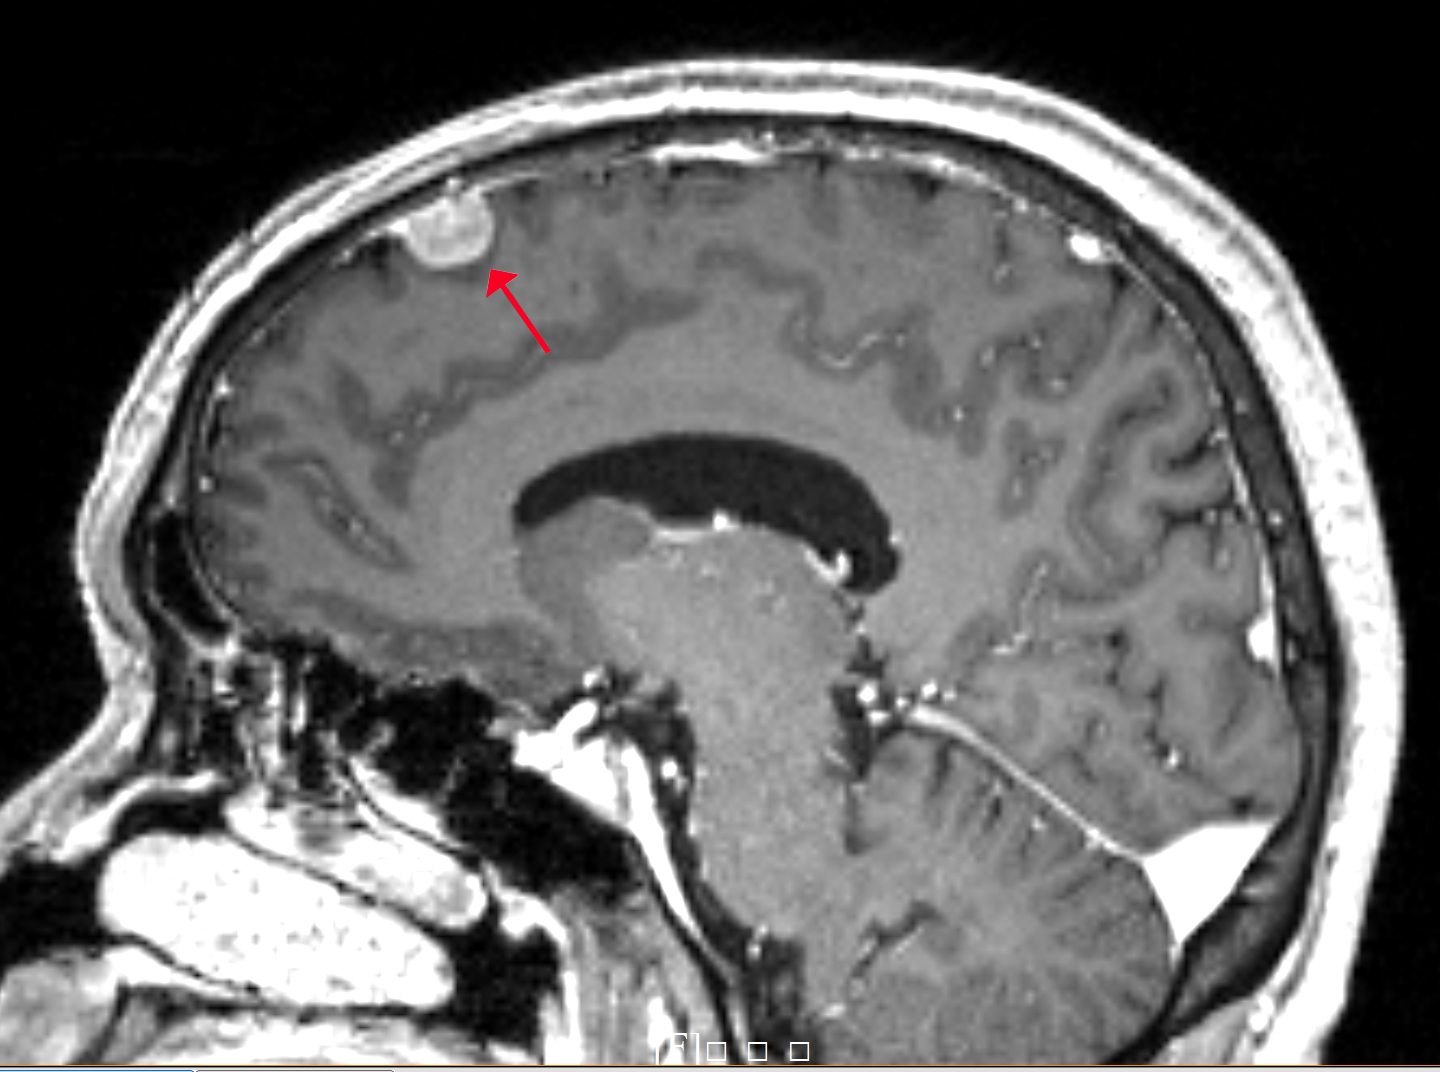

增強磁共振圖像

圖像所見:

顱腦磁共振增強掃描,于腦內右側額部見一枚類圓形明顯均勻強化占位性病變,大小約0.85X1.18X1.42cm,邊界清楚,信號均勻,病灶呈寬基底,于顱骨內板相連,臨近腦回受壓推移,周圍腦溝增寬,可見腦膜尾征。雙側側腦室旁,余腦實質內未見明顯異常。

印象:右側額葉占位性病變,考慮腦膜瘤。